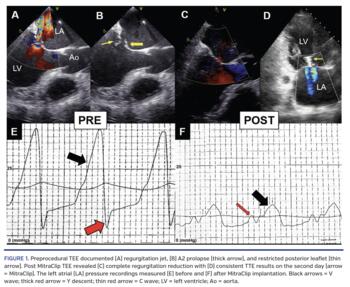

An 85-year-old symptomatic (New York Heart Association class III) male with severe chronic mitral regurgitation (MR), left ventricular ejection fraction of 30%, permanent atrial fibrillation, and high surgical risk (EuroScore II, 13%) was qualified for a MitraClip (Abbott Vascular) procedure. Transesophageal echocardiography (TEE) quantified a regurgitant volume of 68 mL and effective regurgitant orifice of 40 mm2 (Figure 1A). Right ventricular systolic pressure (RVSP) was 51 mm Hg, and both ventricles and atria were dilated. Prolapse of the medial scallop of the anterior leaflet was due to chordae tendineae rupture, whereas partial restriction of the posterior leaflet shortened the length of its mobile portion to 10 mm (Figure 1B). Mitral valve area measured three-dimensionally was 7.1 cm2. The middle scallops of both leaflets were grasped with the single MitraClip device. TEE confirmed MR reduction to a mild degree with gradient of <5 mm Hg (Figure 1C). Left atrial (LA) pressure V wave immediately decreased from 39 mm Hg to 12 mm Hg, reflecting acute hemodynamic changes in passive filling of the LA (Figures 1E and 1F). Moreover, previously deep, negatively deflected Y descent normalized (physiologically reflecting the LA emptying into the left ventricle during ventricular diastole). A small deflection preceding the V wave was most likely a C wave (reflecting bulging of the mitral valve into the LA) previously hidden within the V wave. The morphology may resemble A wave (reflecting atrial contraction), but electrocardiography excluded sinus rhythm. Transthoracic echocardiography on day 2 revealed two small regurgitation jets with RVSP of 41 mm Hg (Figure 1D). Eventually, the patient was deemed New York Heart Association class I. At 1-month follow-up, RVSP was 29 mm Hg and mild residual MR was present.